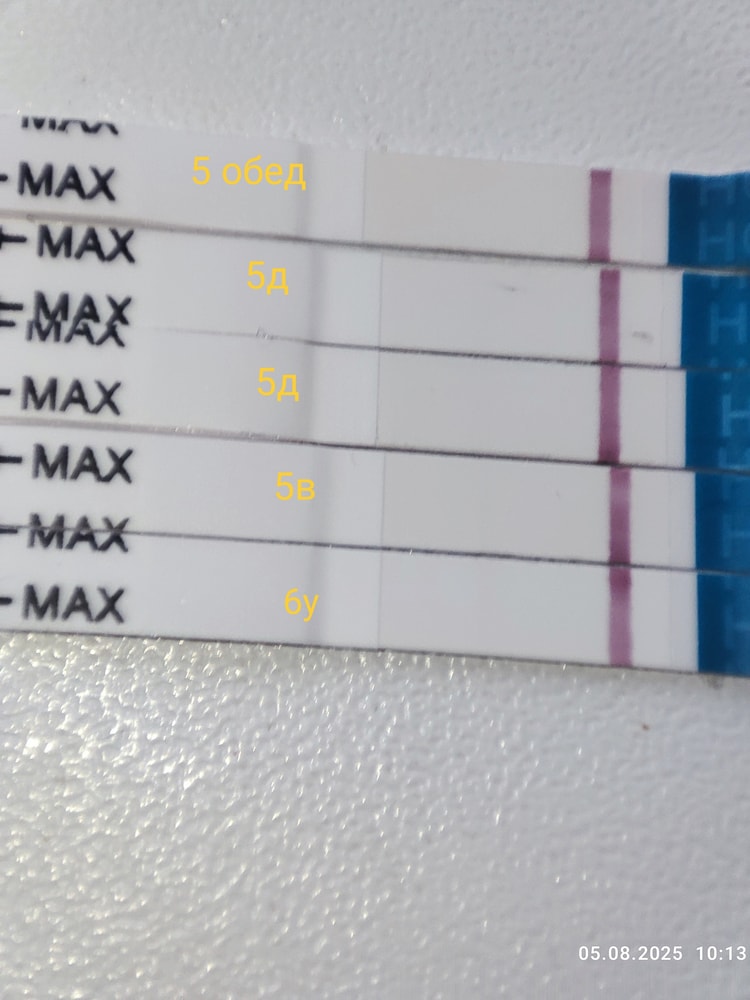

5 дпп 3 бб ЗГТ

Девочки у кого цепляет глаз?

Первые два мама чек

Третий эвик